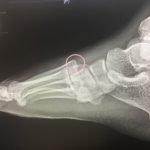

The frontal view of the right foot showed divergent dislocation of the second through fifth metatarsal bones (red outlines) consistent with Lisfranc injury. Though the Lisfranc ligament is not visualized by radiograph, the yellow markings represent the location of the Lisfranc ligament between the medial cuneiform (blue dot) and the base of the second metatarsal bone. The first metatarsal and the medial cuneiform remain congruent. The lateral view shows dorsal dislocation of the midfoot (pink circle) consistent with instability. There is associated extensive midfoot soft tissue swelling.